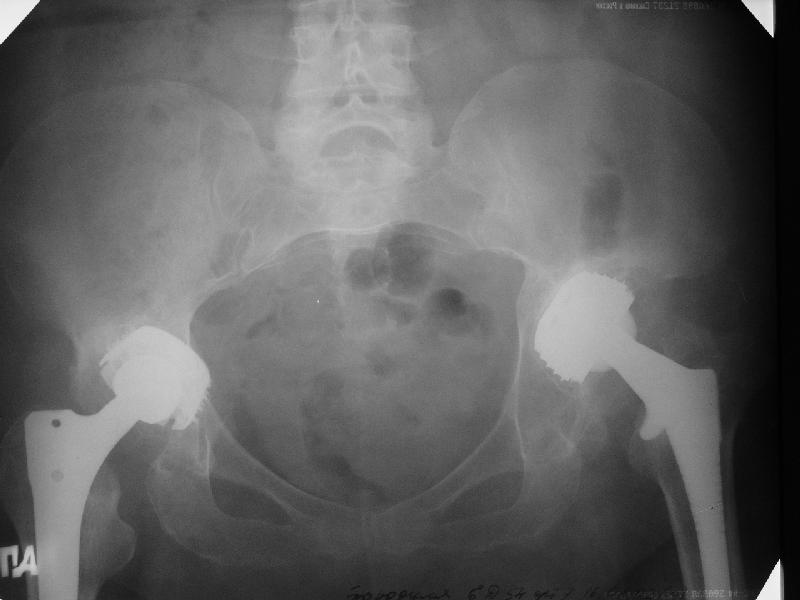

В наше отделение обратилась больная (родственница одного из сотрудников) 1948 г.р. В 2002 г. тотальное эндопротезирование тазобедренных суставов в Кургане.

Август 2002 г.